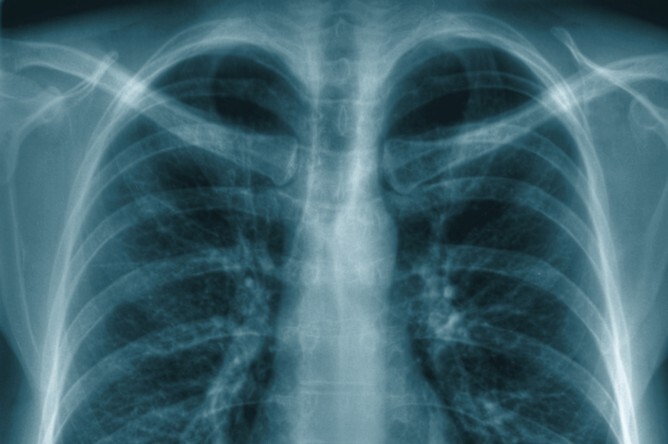

Новое исследование, проведенное исследователями из Онкологического центра Джона Хопкинса Киммела и Школы общественного здравоохранения Джона Хопкинса Блумберга, обнаружило, что секретируемые возрастные изменения в отдаленных участках, таких как легкие, могут активировать спящие клетки рака и вызвать их рост.